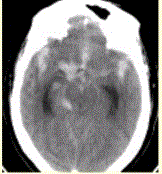

问题 患者男,50岁,突发昏迷、呕吐1h。查体:颈项强直,脑膜刺激征阳性,CT表现如图1。 CTA结果如图2所示,该患者的诊断为

选项 A.动静脉畸形 B.海绵状血管瘤 C.发育性静脉畸形 D.烟雾病 E.基底动脉尖和右侧颈内动脉末端动脉瘤

答案 E